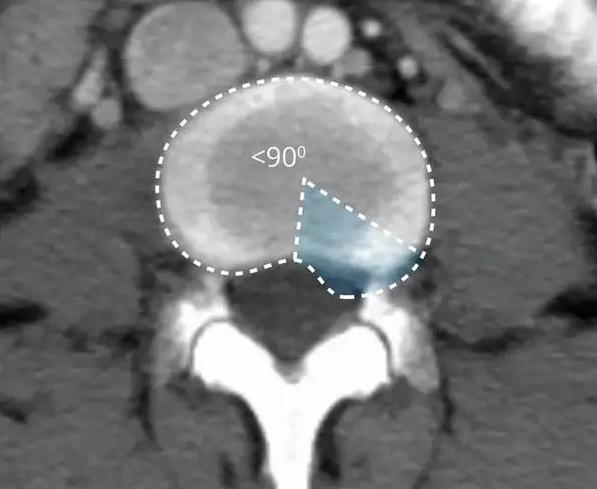

随着年龄的增长或外伤等原因,导致纤维环发生变形或损伤,但是纤维环还没有破碎,外面还是光滑的,只是整体上被压扁了很多,所以俯视看,椎间盘变的膨大了,这就是椎间盘的膨出。

在影像学上表现为纤维环均匀的超出椎体终板边缘。